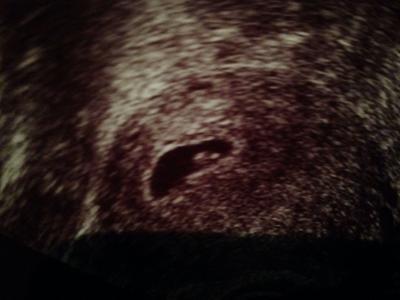

Hi Mädels :) War eben beim Fa und was soll ich sagen 6+3 und das Herzchen schlägt sehr kräftig und ab 13.6 heißt es mupa und los gehts auf ein neues :) Mädels ich bin so happy ^^ bin aufgeregter als bei meiner Tochter vor 1,5 Jahren xD aber es ist sooooo schön ^^ 5,2mm groß das Baby ab jetzt gehts wirklich schnell ^^ Schönen Tag euch :)

Bild zu Zurück vom Fa :) - Forum für Januar - Mamis